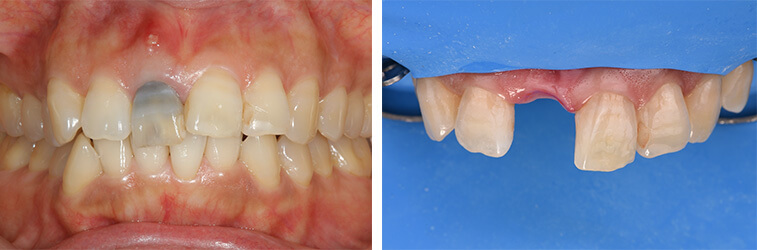

事故により上の前歯がなくなってしまいました。そのままインプラントをするのではなく、矯正治療により歯並びの改善をすることが、インプラントの予後を改善するポイントです。噛み合わせが悪いままインプラントをするとインプラントが後々トラブルを起こすことがあります。

インビザラインによる矯正治療後にインプラント治療を行い、治療終了。先天欠損であった右下の前歯は接着ブリッジによる治療を行いました。

抜歯に伴う骨欠損が大きい場合は、大規模な骨増生が必要になることがあります。